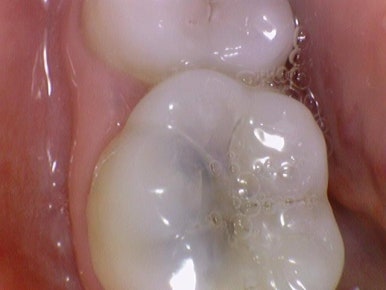

위 엑스레이 치아의 실제 치아 사진입니다.

충치를 제거하면 오히려 까만선으로 보이는 충치보다 치아 겉에서 까맣지 않음에도 불구하고

치아를 많이 파도 남아있을 만큼 더 깊은 충치임을 알 수 있습니다.